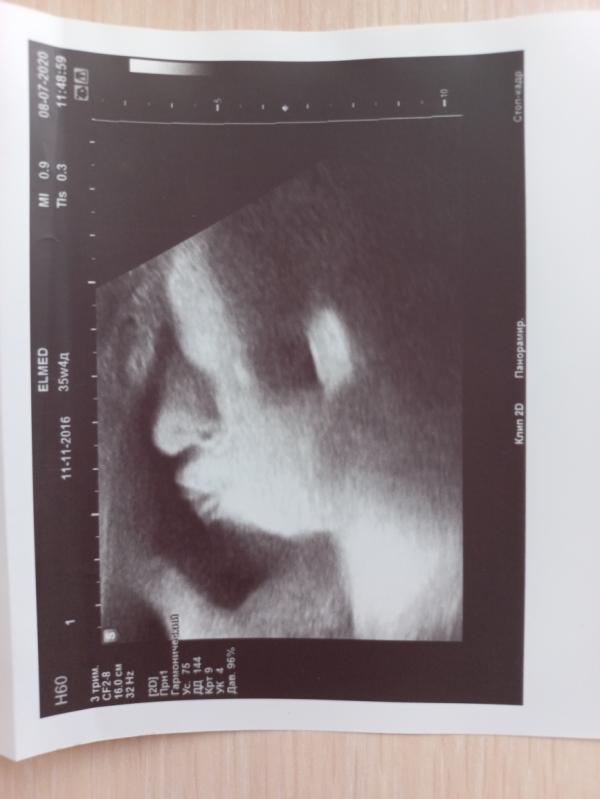

Было 38 недель🤰🙍♀, живот ходил ходуном. Думая что, что-то не так с ребенком, мы с мужем отправились на внеплановое УЗИ.

Всё оказалось хорошо, просто малышка скинула одну петлю с шеи (было двойное обвитие). На радостях спрашиваю: Можно фото ребенка?))

Она (узист) : Ок, только обычно на таком сроке не делаем, ну да ладно, сделаем для вас исключение)))

Ловит ракурс и говорит: Вот👍 отличное фото получилось!!!! 😄 Просто к...